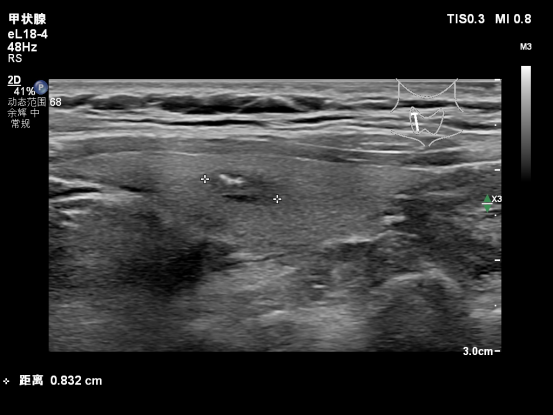

甲状腺结节射频消融 微创精准 不留疤痕 甲状腺结节手术担心留疤? 葫芦岛市第二人民医院 甲状腺疾病诊治中心 超声引导下经皮射频消融术 仅需“一针”即可精准消除结节 不留疤痕,更微创、更精准 守护您的健康与美观 精准诊断,量身定制治疗方案 48岁的张女士在体检中发现甲状腺结节,起初她十分焦虑:既担心结节恶化,又害怕传统手术会留下疤痕、影响甲状腺功能。经过多方咨询,最终慕名来到葫芦岛市第二人民医院甲状腺疾病诊治中心。 甲状腺超声专家门诊超声科王云霞主任、邓兆姝副主任为其完善检查,发现甲状腺存在两枚结节,分别为右叶0.9x0.5cm低回声结节,C-TI-RADS 4b类;左叶0.6x0.4cm囊性结节,C-TI-RADS 2类。 为进一步明确性质,团队为张女士实施了超声引导下细针穿刺活检。经病理检查和BRAF基因检测,确诊为恶性病变。综合她的病情与个人意愿,诊治中心没有直接选择传统手术,而是推荐了更适合她的射频消融治疗方案。这不仅能够彻底灭活病灶,还能最大限度保留甲状腺功能,真正实现“治疗与功能兼顾”。 一针消融,精准守护颈部结构 手术中,王云霞、邓兆姝主任团队先在甲状腺周围注入隔离液,为神经、血管等关键组织筑起一道“安全防护墙”。随后,在超声实时引导下,将消融针精准穿刺至结节部位进行治疗。整个过程患者始终发音清晰,无声音嘶哑等不适,真正做到了“精准消融、周围无忧”。 术后仅十分钟,团队立即为张女士进行超声造影复查。结果显示,消融区域在动脉期及静脉期均无造影剂灌注,呈现“无增强”表现,证实病灶已完全灭活,治疗效果立竿见影。张女士术后恢复顺利,当天即可回家,真正体验到了“当天治疗、当天回家”的便捷。 患者术后 用针眼大小的入口完成治疗,不留疤痕,不影响颈部外观,同时能有效保留正常甲状腺功能,大大缩短了康复时间,提升了治疗体验。 多元选择,一体化诊疗实现个体化治疗 葫芦岛市第二人民医院超声科在王云霞主任带领下,不断精进技术、突破瓶颈。邓兆姝副主任赴北京中日友好医院超声科进修深造后,突破超声诊断技术瓶颈,将前沿诊疗理念与技术引入临床,显著提升了甲状腺穿刺活检的成功率与确诊率。针对甲状腺彩超结节分类4a类以上患者,能够快速精准区分良恶性肿瘤,推动科室甲状腺恶性肿瘤诊断水平实现质的飞跃。 与此同时,超声科积极拓展服务边界,开展甲状腺超声造影、甲状腺囊肿固化治疗、甲状腺消融治疗等多项新技术。自2025年4月甲状腺疾病诊治中心成立以来,甲状腺超声门诊已累计完成穿刺活检近百例,病理及基因检测符合率高达98%,让辽西地区患者在家门口就能享受高水平甲状腺疾病诊治服务。 人民医院 人民名医 王云霞 副主任医师 ·葫芦岛市第二人民医院超声科主任 ·中国研究型医院学会委员 ·中国研究型医院学会肌骨及浅表专业委员会超声学组委员 ·中国女医师协会委员 ·辽宁省超声医学工程学会理事会理事 ·辽宁省医师协会超声分会委员会委员 ·辽宁省免疫学会超声治疗分会委员 ·辽宁省中西医结合委员会超声分会委员 ·葫芦岛市医学会超声委员会副主委 专业特色:擅长心血管和外周血管、浅表器官和腹部及产前超声诊断;超声引导下前列腺癌、肺癌及淋巴癌穿刺活检病理标本的采集;心包、胸(腹)腔积液的穿刺引流;介入治疗肝肾脓肿胆囊置管引流;超声引导下甲状腺、乳腺结节的细胞学及组织学穿刺活检;甲状腺、卵巢及肝肾囊肿的固化治疗等,盆底超声、实质器官及血管超声造影以及部分肌骨超声检查。发表核心级论文2篇、国家级论文6篇,参与编撰图书一部,《医学影像诊断指南》副主编。 邓兆姝 副主任医师 ·葫芦岛市第二人民医院超声科副主任 ·中国研究型医院学会肌骨及浅表超声科专业委员会青年委员 ·辽宁省医学会超声医学分会委员 专业特色:甲状腺、乳腺疾病超声精准诊断;超声引导下穿刺活检(细针/粗针);全身脏器超声造影;甲状腺、乳腺及其它脏器囊肿硬化治疗;甲状腺癌术后超声随访评估;独立开展甲状腺结节微波/射频消融治疗。 技术特色:开展甲状腺结节多模态超声评估(弹性成像+造影)、消融治疗全程超声监控等特色技术,以“精准诊断+微创治疗”为临床特色。